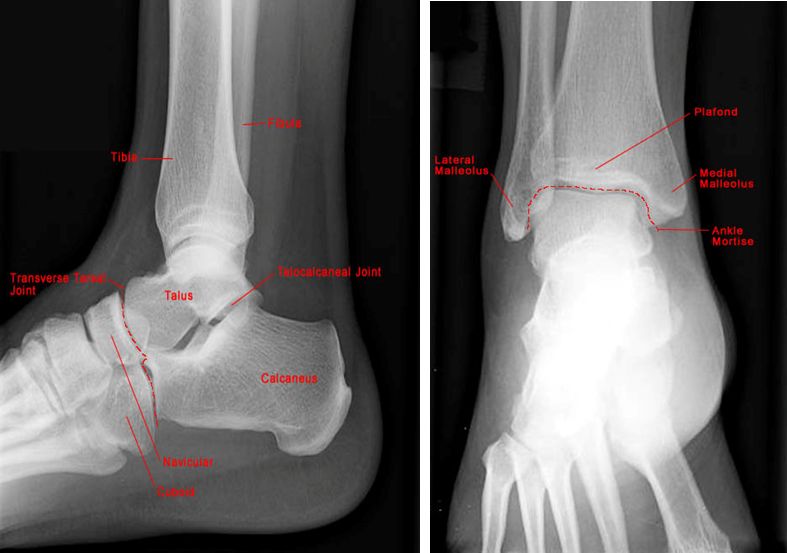

正常踝关节

疼痛科怎么理疗疼痛科医生、康复理疗科医生、针刀针灸医生应掌握的常见骨科疾病X光片_https://www.jmylbn.com_新闻资讯_第38张